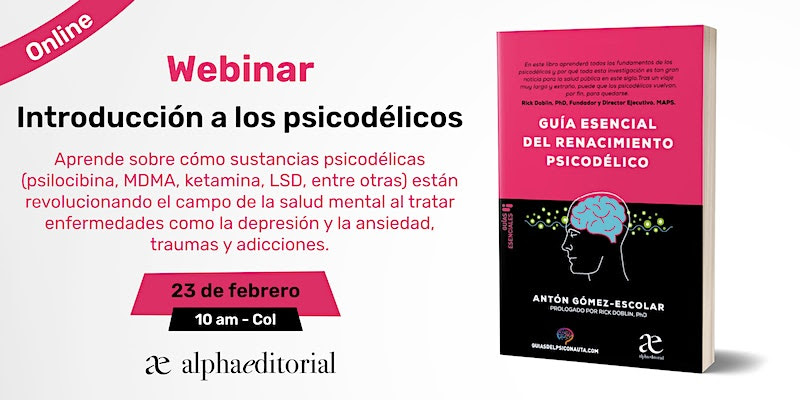

Silicon Valley y la revolución psicodélica: ¿una nueva cultura laboral?

Silicon Valley, cuna de la innovación tecnológica, está experimentando una transformación silenciosa pero profunda: la integración de los psicodélicos en la cultura laboral. Lo que hace años se consideraba marginal o subversivo, hoy se ha convertido en una herramienta legítima para potenciar la creatividad, combatir el agotamiento y redefinir el bienestar en la meca tecnológica. De la marginalidad a la integración terapéutica La llamada integración psicodélica, guiada por terapeutas especializados, es ahora una práctica común entre ingenieros, emprendedores y ejecutivos del sector tecnológico.